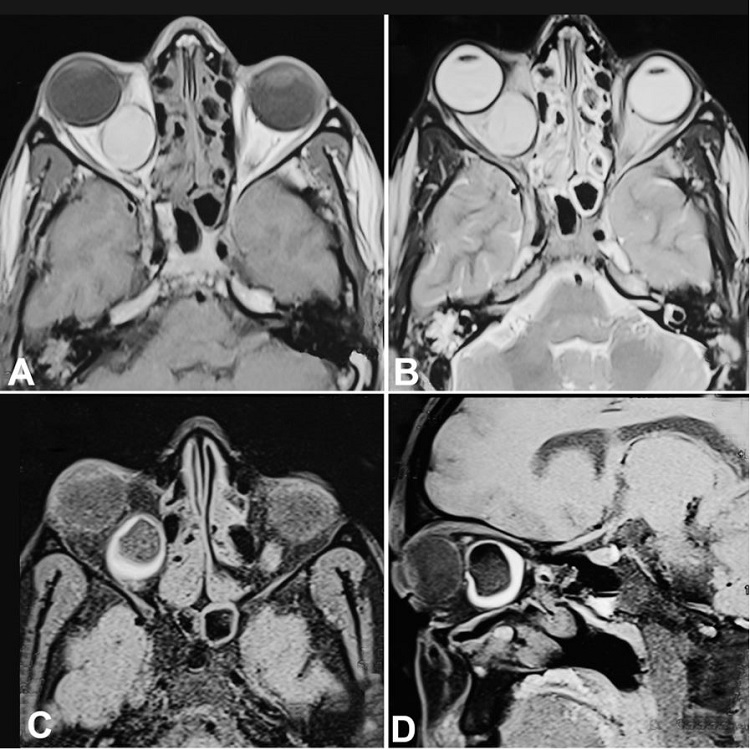

A 30-year male presented to the outpatient department with pain and bulging over the right eye for 3 months and diplopia for 2 months (Figure 1). There was no abnormality in the visual acuity. Restriction of eye movement was detected towards the right lateral gaze. The otoscopic examination was found normal. There was no significant neurological deficit. Ophthalmic examination revealed normal visual acuity and field of vision except axial proptosis. The contrast-enhanced MRI scan of the orbit and brain revealed a 3.0 cm well-defined retrobulbar cystic mass occupying the whole intraconal space on the right side, displacing the optic nerve superolateral and the medial rectus in the medial aspect without any intracranial extension. The adjacent bony structures were found intact without any erosion or hyperostosis. On the MRI, the mass was hyperintense in both T1-weighted and T2-weighted images (Figure 2A and 2B). Again, T1- weighted image with a fat-saturated sequence revealed hypointense signals due to the presence of the fat component in the dermoid cyst (Figure 22D).